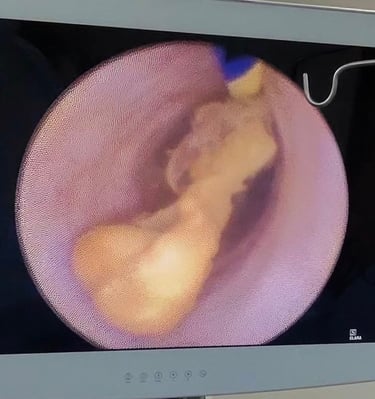

Galería

Imágenes que reflejan cuidado y confianza.